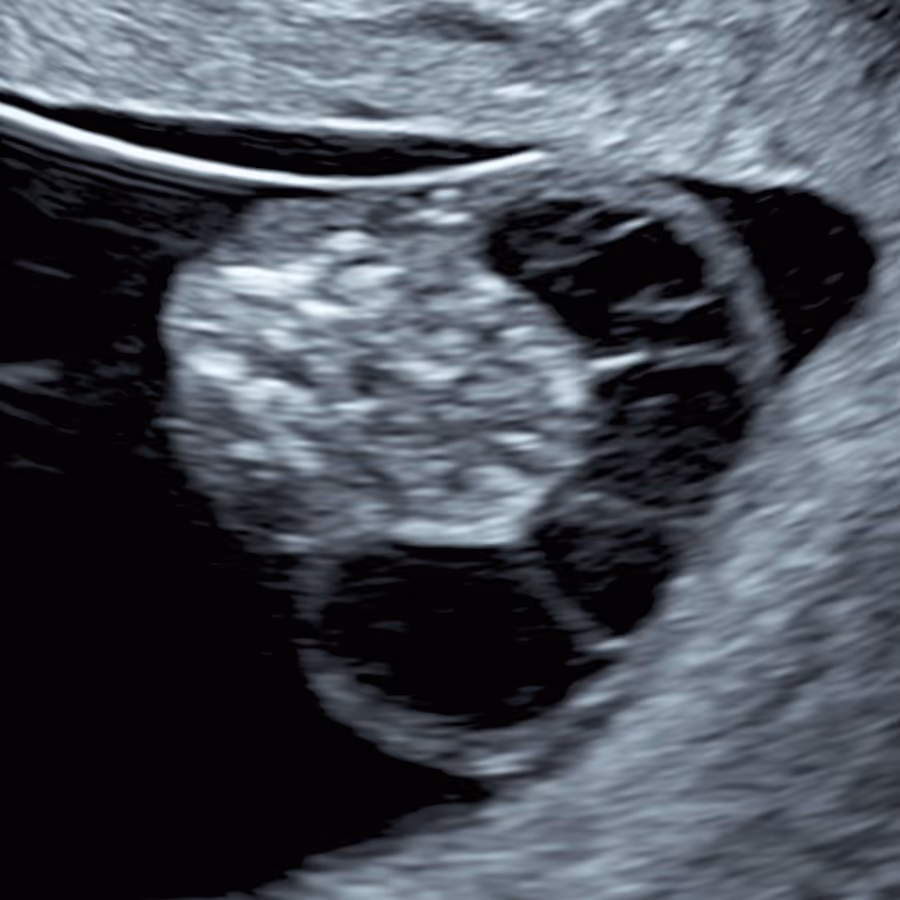

iNT denotes increased NT at 10 weeks (CRL <45 mm), defined as NT ≥2.5 mm - abnormal and strongly linked to adverse outcomes. The lower cut-off than at 11–14 weeks (3.5 mm) reflects smaller fetal size at this early stage of gestation.

Unfortunately, yes. Around 42% of babies with increased NT at 10 weeks (iNT) have serious health problems, including chromosomal or genetic syndromes, structural anomalies, or miscarriage. The risk rises with NT thickness about 30% for 2.5–3.4 mm, 50% for 3.5–4.4 mm, and 70% for 4.5 mm or more. These risks are higher than at 11–14 weeks.